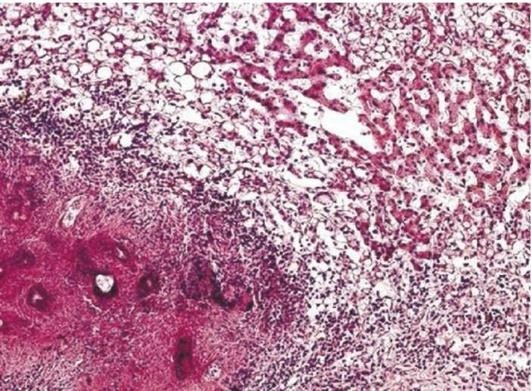

Уже через несколько часов после начала гнойного воспаления вокруг скопления экссудата виден вал из клеток крови: моноцитов, макрофагов, лимфоцитов, эозинофилов, скоплений фибрина. При этом на фибрине происходит осаждение циркулирующих иммунных комплексов, которые являются хемоаттрактантами для комплемента, обладающего выраженными гистолитическими свойствами. Кроме того, комплемент - это хемоаттрактант для полиморфно-ядерных лейкоцитов, он стимулирует их эмиграцию из сосудов и поступление в очаг воспаления. Фибрин и комплемент - основа для формирования так называемой пиогенной мембраны, которая является внутренним слоем будущей соединительнотканной капсулы абсцесса. Разумеется, здесь не образуется гной, но из-за хемотаксиса лейкоциты поступают в очаг воспаления из сосудов и вначале концентрируются в области внутреннего слоя капсулы. Через 3-е суток вокруг абсцесса начинается формирование грануляционной ткани, которая созревает в соединительнотканную капсулу, имеющую 2 слоя: внутренний, обращенный в полость, состоящий из грануляций, фибрина, детрита, и наружный - из зрелой соединительной ткани. Через сосуды грануляционной ткани также происходит поступление в полость абсцесса лейкоцитов и частичное удаление из нее продуктов распада. На формирование капсулы абсцесса оказывает влияние состояние иммунитета - при иммунодефиците у пациента образуется неполноценная капсула, появляется склонность к расплавлению тканей, окружающих абсцесс, что является предпосылкой для развития флегмоны.